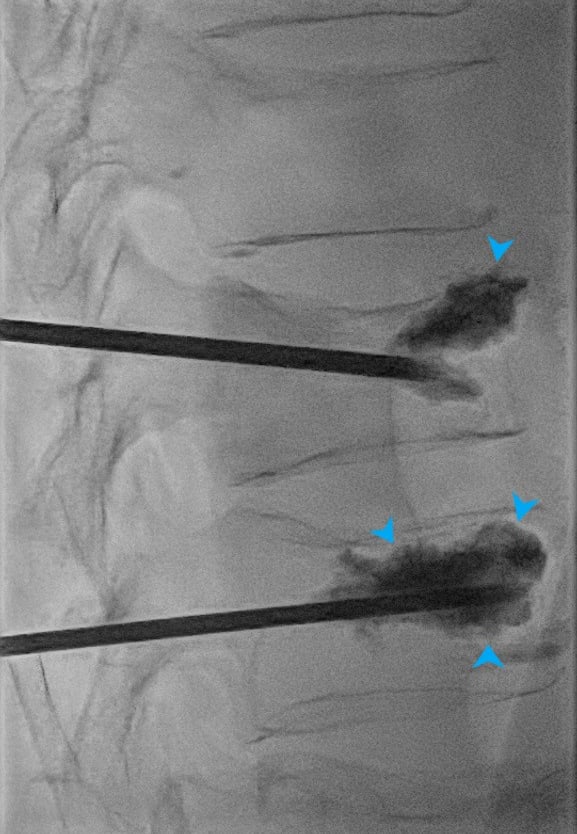

Le ciment est en suite injecté à travers l'aiguille jusqu'au bon remplissage de la vertèbre. L'injection est surveillée par les images de radiographie pour éviter les fuites de ciment.

Cimentoplastie percutanée réalisée dans notre centre : Photo 1 : aiguilles en place dans chaque vertèbre fracturée. Photo 2 : injection du ciment visible en radiographie (têtes de flèches bleues).

Le risque principale est la fuite extra-osseuse de ciment lors de son injection. Même si ces fuite sont fréquentes, elles sont pour la grande majorité sans conséquences. Le radiologue est vigilent lors de la procédure pour les dépister, et les fuites symptomatiques sont donc devenues exceptionnelles.